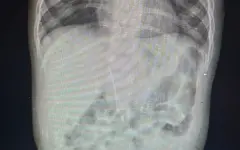

09:22 24.01.2026 Общество Иглу нашли в брюшной полости младенца в Туркестане В Туркестане врачи спасли восьмимесячного младенца, у которого в брюшной полости обнаружили иглу, передает ИА «NewTimes.kz» со ссылкой на Otyrar.kz. больницаребенокТуркестанская область Читать